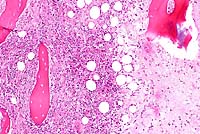

4x

obj

10x

40x

- Case 20-3. Tumor. Normal bone is replaced by streams

& bundles of spindle cells and multifocal clusters of multinucleate

giant cells.